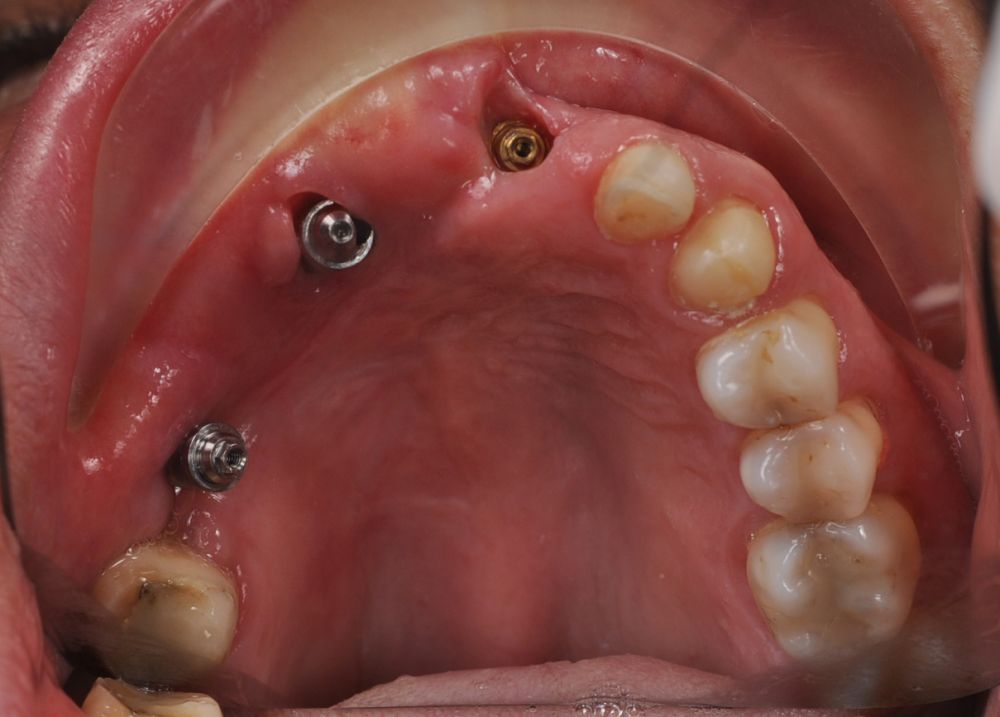

Una vez finalizada la radioterapia, la paciente se encontraba libre de enfermedad. Por lo que se procedió a la restauración definitiva implantosoportada. Tras la segunda fase, se colocaron dos pilares transepiteliales Multiunit Ò rectos y un pilar Multunit Ò angulado de 17º (Figura 10).

Para la fabricación de las estructuras, se eligió el óxido de zirconio monolítico como material restaurador sobre interfases metálicas en el puente implantosoportado, y coronas de óxido de zirconio monolítico en los dientes tallados previamente (1.7, 1.6, 2.2 y 2.3). Se tomaron impresiones de cubeta abierta con silicona de adición pesada y fluida (Zhermack Elite HD, Gmbh). Se realizó una prueba de pasividad analógica y el resto del proceso se confeccionó de manera digital, por lo que se hicieron pruebas estéticas de dientes impresas en 3D sobre interfases metálicas, para hacer todos los ajustes de función y estética previos al fresado del zirconio monolítico (Figuras 11, 12 y 13).

El día de la colocación de las estructuras, se arenó el interior de las coronas dentosoportadas con óxido de aluminio de 50 m y fueron cementadas con cemento de resina Multilink Ò. El puente implantosoportado se atornilló al torque indicado (20Nw) (Figuras 14, 15, 16 y 17).